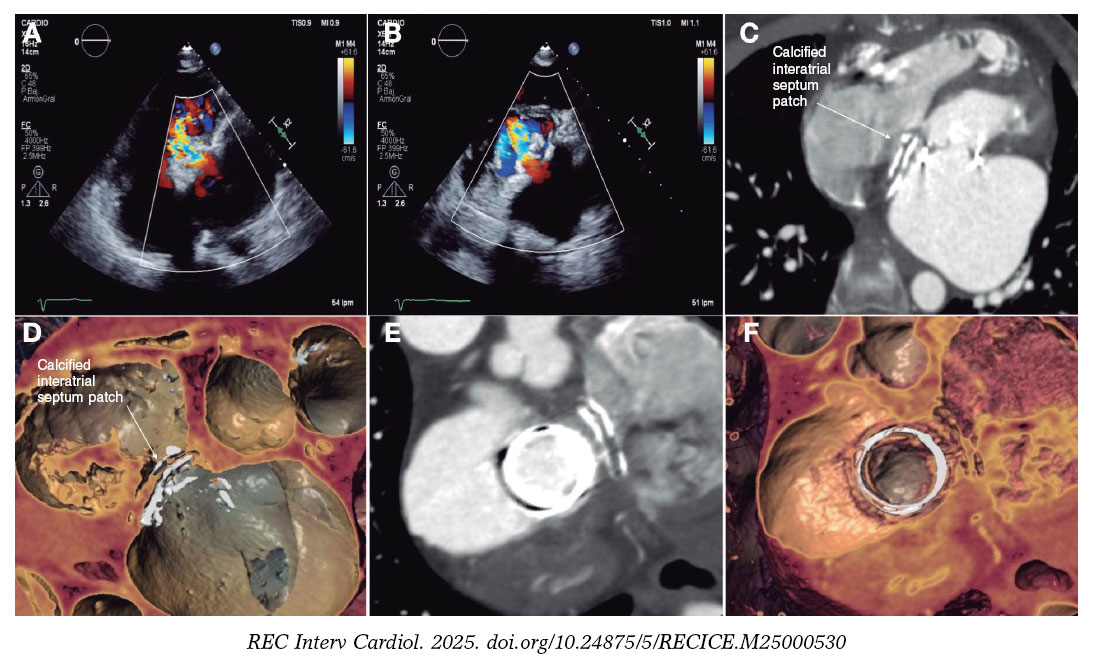

A 55-year-old woman with an incomplete atrioventricular canal, who underwent repair of the mitral cleft and patch closure of the ostium primum type defect, followed by mitral bioprosthesis implantation (Carpentier PERIMOUNT 27, Edwards, United States) in adulthood. She developed episodes of left atrial flutter. Due to the inability to perform a transseptal puncture, we proceeded with retroaortic atrioventricular node ablation, resulting in iatrogenic left main coronary artery dissection, which resolved after drug-eluting stent implantation (figure 1A-D, videos 1 and 2 of the supplementary data). During follow-up, she showed signs of progressive prosthetic degeneration (figure 2A-B, videos 3 and 4 of the supplementary data), which led to transcatheter mitral valve-in-valve implantation. We performed a transseptal puncture of the severely calcified patch (figure 2C-D) using a Versacross system (Boston Scientific, United States). Then, we used a deflectable catheter to advance a high-support guidewire, which was, eventually, captured in the left ventricle, establishing a venoarterial loop. Afterwards, we performed a septostomy with an Atlas Gold 16 mm × 45 mm balloon catheter (BD, United States) and with great difficulty given the anatomical complexity, we advanced a 26-Fr DRYSEAL sheath (Gore, United States) into the left atrium through which we implanted a SAPIEN 3 Ultra 26 bioprosthesis (Edwards, United States) with a nominal +2 cm³ inflation. Good expansion was observed, with slight protrusion into the left ventricle without conflict with the outflow tract (figure 3A-D, video 5 of the supplementary data). The patient was discharged with normal prosthetic valve function, which was maintained at the 1-year follow-up (video 6 of the supplementary data). The patient signed the informed consent form.

Figure 2.